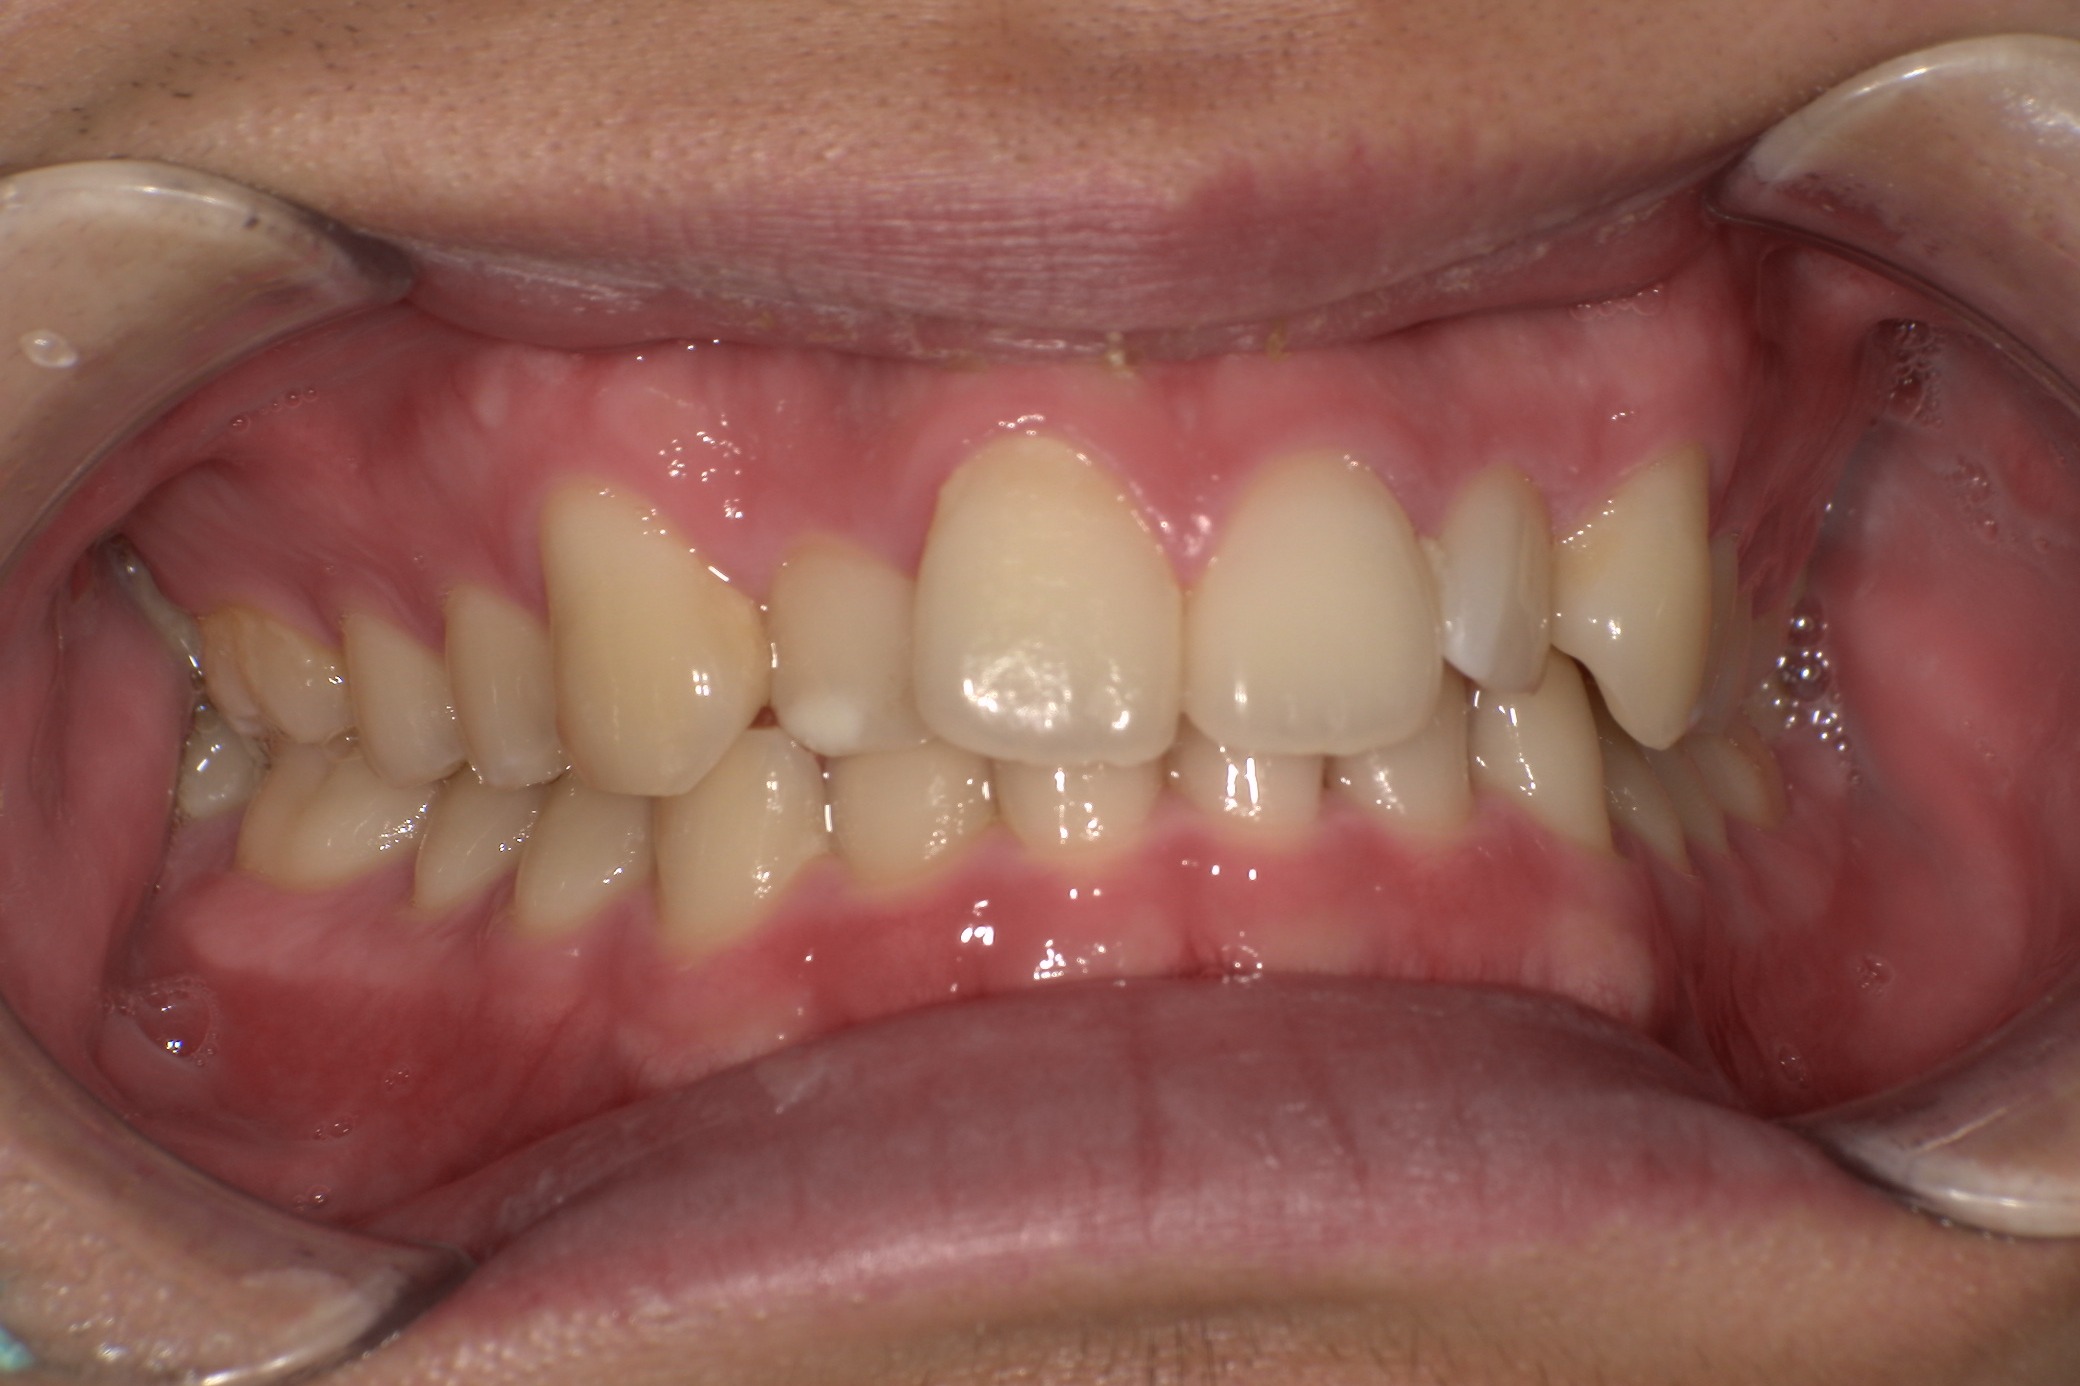

歯並びがコンプレックスで友人と写真を撮る際も気にしてしまっていたという20歳の男子大学生I.T.様にのI.T.様。始めやすい価格と目立ちにくさからスマイルモア矯正を選び、自信を持って笑えるようになった経緯を伺いました。

矯正を始めようと思ったきっかけを教えてください。

長年、自分の歯並びにコンプレックスがあり、友人と写真を撮るときもいつも歯並びを気にしてしまっていたんです。自信を持って笑えないことが一番の悩みでした。 この悩みを解消し、将来的な歯や口の健康も考えて、矯正を始めようと思いました。